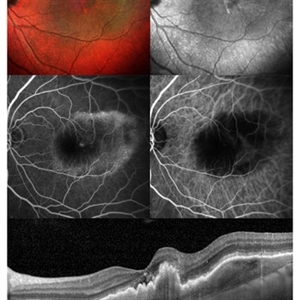

Neovascular AMD

Multicolor image and infra-red image showing fibrovascular pigment epithelial detachment (PED),FFA and ICG confirms the diagnosis., SD-OCT shows notched fibrovascular PED

Photographer: Puttaswamy,Ravikrishna

Imaging device: Heidelberg Spectralis

Condition/keywords: neovascular age-related macular degeneration (AMD)